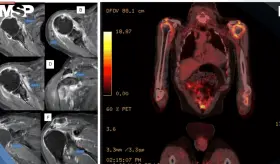

Las lesiones óseas osteolíticas, anemia y alteraciones hematológicas h...

Aunque incurable, esta neoplasia de células plasmáticas ya se controla de forma crónica gracias a innovaciones como anticuerpos monoclonales y terapias CAR-T, accesibles en Puerto Rico

Especialista explica qué es esta malignidad de células plasmáticas, cómo se detecta y por qué los avances en tratamientos han transformado radicalmente el pronóstico de los pacientes.